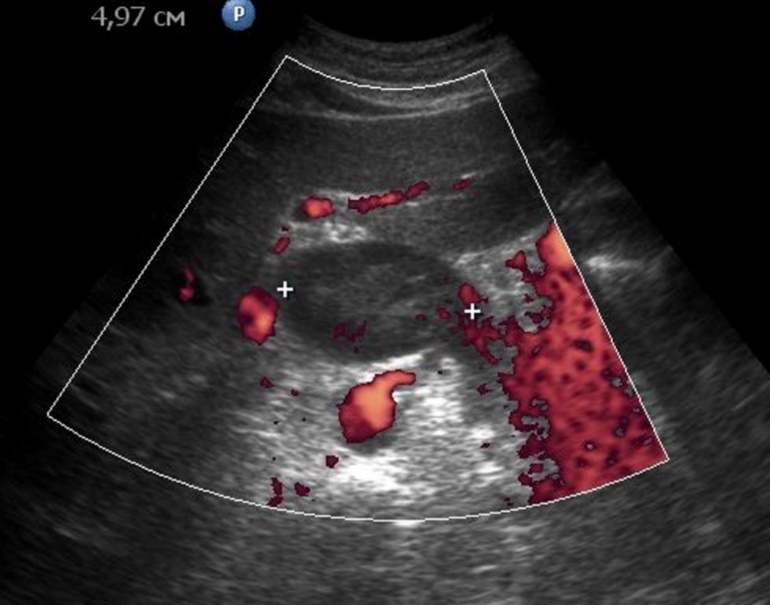

Metastasis to the regional lymph nodes was diagnosed in 52 cases. Ultrasonographically, this was detected in 37 (71.2%) cases. Sonographic features of lymph node metastatic lesions are: an increase in their thickness, a decrease in echogenicity, deterioration or lack of differentiation of the peripheral and central parts of the nodes, recording of color vascular signals inside the nodes (Figure 18, Figure 19).

Figure 18.Metastasis to the retroperitoneal lymph node in gastric cancer of the antrum of T3 stage. The longitudinal size of the lymph node is increased to 5 cm, the echo is significantly reduced, along the periphery of it is visible color vascular signals in tissue Doppler mode.